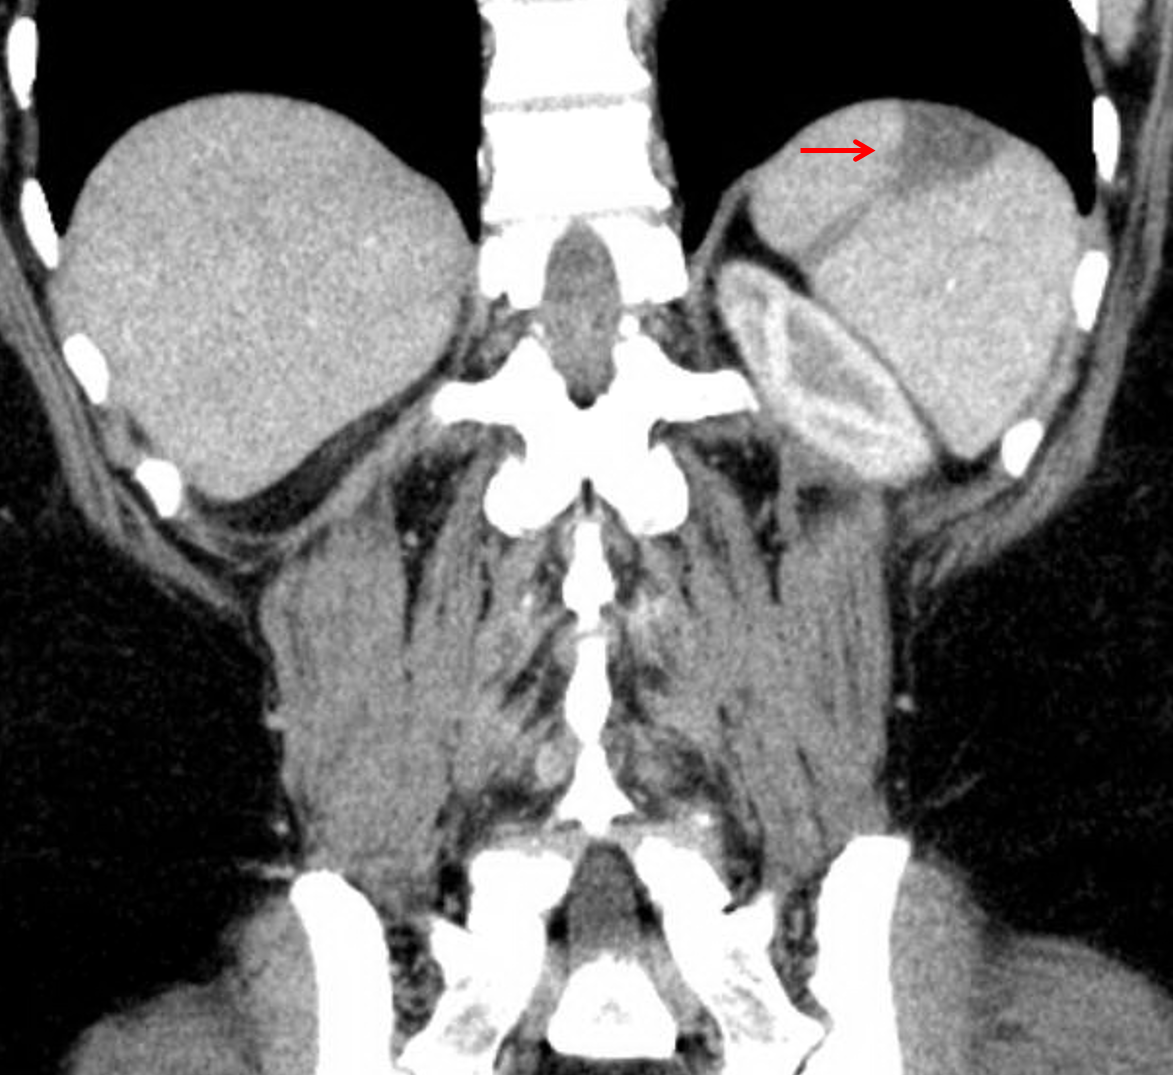

Age: 51

Sex: Female

Indication: Left upper quadrant pain

Sample ReportNo acute findings to explain left upper quadrant pain.

Remote appearing splenic infarct.